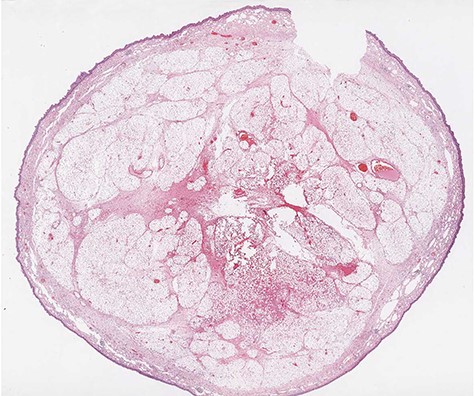

Microscopic transverse section of the pedunculated lipoma composed by mature adipocytes, interspersed by blood vessels, surrounding a central fibrovascular axis; Tumor covered by intact esophageal squamous mucosa. No spindle cells are present. (H&E stain, ×4).